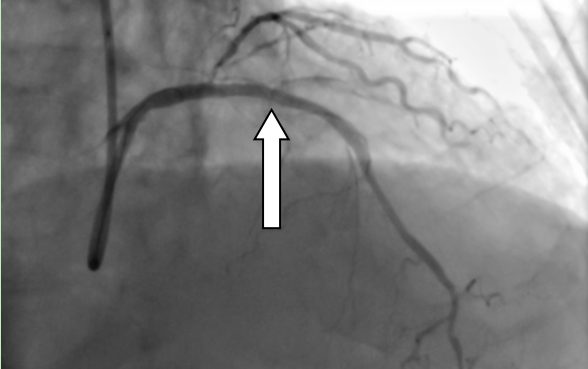

▲冠状动脉内膜旋磨术进行中。 通俗说钙化:血管里的“水垢”是什么? 提到冠心病,大家并不陌生,但冠脉钙化是什么?简单来说,就像家里用了几十年的水管,内壁会慢慢结满厚厚的水垢,血管也会因年龄增长、代谢变化,在血管壁上形成坚硬的钙化斑块——这种斑块质地坚硬,会不断变厚、缩小血管管腔,导致心脏供血不足,严重时会引发胸痛、心肌缺血,甚至危及生命,对高龄老人来说,风险更为突出。 九旬老人的难题:血管堵得只剩细缝 冯伯的案例就是典型的高危冠脉钙化情况。他因反复胸痛就医,冠脉造影检查发现,心脏三支主要供血血管均出现病变,其中最关键的供血血管——左前降支,近中段布满了厚厚的钙化斑块,血管狭窄程度高达95%,心脏供血已严重受限。更关键的是,93岁的高龄让他的血管变得壁厚、质硬、弹性差,形成了“高阻力钙化病变”,给治疗带来了极大难度。 ▲造影显示患者血管血管狭窄程度高达95%。 很多人会问,普通的心脏介入手术不能解决吗?我院心血管内科一区专家解释:“严重钙化的血管就像结满厚水垢的老旧水管,僵硬又狭窄,常规的球囊扩张术,就像用气球去吹硬邦邦的水管,根本无法将钙化斑块撑开,强行操作还可能导致血管撕裂、损伤,反而增加风险。” 对付硬钙化:“金刚钻”来帮忙 面对这种高难度的钙化病变,冠状动脉内膜旋磨术就成了针对性的治疗方式。针对冯伯的病情,医疗团队经反复评估后,决定采用这项技术为他治疗,而这项技术,也是目前应对坚硬冠脉钙化的常用微创手段之一。 冠状动脉内膜旋磨术的原理并不复杂,核心就是用“金刚钻”样的工具,精准磨掉血管内的坚硬钙化斑块。手术时,医护人员会通过微创方式,将一根顶端镶有微小钻石颗粒的橄榄型旋磨头,送入堵塞的血管内,让旋磨头以极高的速度旋转,将坚硬的钙化斑块研磨成直径小于5微米的微小微粒——这种微粒比红细胞还要小,会随着血液循环被人体自身的吞噬细胞清除,不会对身体造成额外伤害,从而打通堵塞的血管通路。 虽然原理简单,但这项手术对操作精度要求极高:既要彻底磨碎钙化斑块,打通血管通路,又要小心翼翼保护血管内壁,避免造成血管损伤。手术中,医疗团队全程精准操控旋磨头,顺利完成旋磨术后,又通过植入药物洗脱支架,进一步巩固治疗效果,防止血管再次狭窄。 术后恢复:老人终于不胸痛了 术后复查结果显示,支架贴合良好,原本严重堵塞的血管恢复了通畅,冯伯的胸痛症状缓解,心脏供血恢复正常,精神状态也日渐好转,最终顺利康复出院。 ▲支架植入术后,冠脉恢复正常供血。 结合这个案例,我们可以了解到一个重要的知识点:高龄并非复杂冠脉钙化介入治疗的绝对禁区。我院心血管内科一区主任医师陈文广表示,这类手术的成功,离不开术前精准的病情评估、术中娴熟的操作技巧以及多学科的密切配合,而这也为高龄冠脉钙化患者的治疗提供了可行的思路——经严格评估后,合适的微创技术可以有效解决这类心脏难题。 温馨提示: 正视血管钙化,及时就医 随着人口老龄化加剧,高龄、高危冠脉钙化患者越来越多,也让这类心脏问题受到更多关注。冠状动脉内膜旋磨术等微创技术的应用,不仅为这类患者提供了更多治疗选择,也让我们意识到,科学认识冠脉钙化、及时规范就医,才能更好地守护老年人群的“心”健康。 心血管内科一区简介 基本概况 我院心血管内科一区现有医护人员32名,开放床位46张,其中重症监护室(CCU)床位14张。科室配备数字减影血管造影机、血管内超声仪、血管内旋磨仪、主动脉内球囊反搏仪、心排血量监测仪等专业医疗设备,为临床诊疗工作提供硬件支持。 诊疗技术 科室在冠心病、心力衰竭、心律失常、主动脉夹层、心脏瓣膜病、心肌病、外周血管闭塞性疾病等心血管疾病的诊疗方面积累了丰富经验,针对急性心肌梗死、心源性休克、急慢性心力衰竭、主动脉夹层或动脉瘤、严重心律失常等急危重症病例,开展规范的诊断与救治工作。 临床工作中,科室常规开展心血管介入检查及治疗项目,包括冠脉支架植入术、冠脉血管内旋磨术、心脏射频消融术、主动脉腔内隔绝术、永久起搏器植入术、下腔静脉滤器植入术、肾动脉支架植入术、下肢动脉支架植入术等。 科室曾在“县域中国医院品牌专科评选”中获评第二名,先后获得“阳江市青年文明号”称号,连续多年被评为医院先进科室,团队始终秉持严谨务实的工作作风,为患者提供专业的医疗服务。 专家简介 陈文广 心血管内科主任医师,心血管内科一区主任、教授,心血管介入学科带头人、胸痛中心医疗总监。 担任广东省医师协会心脏病器械辅助治疗医师分会第三届委员会常务委员、广东省医师协会心血管内科医师分会第四届委员会委员、广东省卫生经济学会心血管疾病分会常务委员、广东省中医药学会心力衰竭专业委员会第二届常务委员、广东省基层医药学会中西医结合心血管专业委员会第二届常务委员、广东省中西医结合学会心血管介入专业委员会委员、广东省中医药学会心脏血脉专业委员会委员、广东省医师协会心脏起搏与电生理专医师分会第二届委员会基层医院心脏起搏与电生理专业组成员,阳江市医学会心脏介入分会第二届委员会副主任委员、,阳江市医学会心血管内科分会第二届委员会副主任委员、阳江市医师协会心内科医师分会第二届委员会副主任委员等。参与国家级临床科研项目1项,省级及市级临床科研项目多项;撰写著作多本,发表10多篇省级以上论文。 擅长领域:从事心血管疾病介入治疗10多年,累计有5000多例冠状动脉支架植入术(PCI)的手术经验。擅长冠心病、高血压、心衰、主动脉夹层、心脏瓣膜病、心律失常等心血管疾病的诊治,熟练掌握冠心病、左主干病变、多支血管病变、高危病变、钙化、分叉、慢性闭塞病变、临时及永久起搏器植入、主动脉覆膜支架腔内隔绝术、下腔静脉滤器植入、外周血管介入治疗等介入技术治疗。 崔 跃 心血管内科副主任医师,心血管内科一区副主任。 广东省医师协会高血压分会委员、阳江市医学会心血管分会常务委员、阳江市医学会心脏介入分会常务委员、阳江市医师分会心血管分会常务委员。参与国家级临床科研项目1项,市级临床科研项目3项;撰写著作1本,发表6多篇省级以上论文。曾多次到上级医院心血管内科进修学习,其中到中山大学第一附属医院进修心血管重症班,另先后三次到南方医院附属珠江医院进修学习心血管介入技术。 擅长领域:熟练掌握心血管介入技术,独立完成冠状动脉造影手术和冠状动脉介入手术,擅长心肌梗死、恶性心律失常、急重症心衰等的抢救。 黄 毅 心血管内科副主任医师,介入科副主任,胸痛中心秘书及协调员。 广东省胸痛中心协会委员、广东省介入学会结构性心脏病分会委员、广东省健康管理学会肺血管病专业委员会委员、阳江市医学会心血管内科分会常务委员、阳江市医学会心脏介入分会常务委员、阳江市医师协会心内科医师分会委员,阳江市医学会心脑同治分会常务委员。主持阳江市卫生健康局科技研究立项1项,主持阳江市科学技术局科技研究立项3项,参与阳江市科学技术局科技研究多项。主编《高血压及相关疾病现代诊疗》,发表国家级专业论文4篇、省级专业论文2篇。2010年毕业于广东医科大学临床医学专业,毕业后一直从事心血管内科工作,曾先后到南方医科大学珠江医院进修学习冠心病介入技术(PCI)和广东省人民医院心研所(国家班)进修结构性心脏病(包括先天性心脏病介入封堵、左心耳封堵、二尖瓣狭窄球囊扩张、肺血管病介入等)。 擅长领域:主要致力于冠心病介入、结构性心脏病介入(包括先天性心脏病介入封堵、左心耳封堵、二尖瓣狭窄球囊扩张、肺血管病介入等)、B型主动脉夹层介入、下肢动脉闭塞介入、高血压、急慢性心力衰竭、肺动脉高压的诊断与治疗。 许军国 普通内科副主任医师。 阳江市医学会心血管分会委员、阳江市医师分会心血管分会委员。1996年广东医学院临床医学毕业。曾到暨南大学第一附属医院进修重症医学科,2020年在中山大学附属第一医院进修心血管重症科CCU。 擅长领域:从事心血管疾病诊治工作25年,擅长心血管疾病重症治疗,在冠心病心肌梗死、高血压、心律失常、心力衰竭等疾病治疗上有丰富临床经验。 李昌利 心血管内科副主任医师。 阳江市医学会脑心同治分会第二届委员会常务委员、阳江市医学会心血管内科分会委员、阳江市医学会心脏介入分会委员、阳江市医师协会心内科医师分会委员。毕业于广东医学院(今广东医科大学),毕业后在阳春市人民医院工作至今。 擅长领域:擅长治疗高血压病、冠心病、心力衰竭、房颤、下肢静脉血栓等心血管疾病。 张智华 心血管内科副主任医师。 阳江市医学会脑心同治分会第二届委员会常务委员、阳江市医学会心血管内科分会委员、阳江市医学会心脏介入分会委员、阳江市医师协会心内科医师分会委员。毕业于广东医科大学临床医学专业,2016年到南方医科大学珠江医院进修学习冠心病介入技术。2021年在中山大学附属第一医院进修心血管内科。 擅长领域:擅长冠心病、高血压、心力衰竭、心律失常的诊断与治疗,熟练掌握冠状动脉介入操作及冠状动脉介入治疗技术。 滕 超 心血管内科主治医师。 阳江市医学会脑心同治分会第二届委员会常务委员、阳江市医学会心血管内科分会委员、阳江市医学会心脏介入分会委员、阳江市医师协会心内科医师分会委员。毕业于广西中医药大学,2019年到广东省人民医院进修学习冠心病介入技术。 擅长领域:擅长冠心病、高血压病、心力衰竭、下肢深静脉血栓形成等疾病的诊治。熟练掌握冠状动脉造影及冠状动脉介入治疗技术。 莫介超 心血管内科主治医师。 阳江市医学会脑心同治分会第二届委员会常务委员、阳江市医学会心血管内科分会委员、阳江市医学会心脏介入分会委员、阳江市医师协会心内科医师分会委员。毕业于广东医科大学临床医学专业,2016年到南方医科大学珠江医院进修学习心血管内科,2023年到中山医科大学附属第一医院进修心律失常介入技术。 擅长领域:擅长心律失常、冠心病、心力衰竭、高血压等疾病的诊断与治疗。 刘艺豪 心血管内科主治医师。 阳江市医学会脑心同治分会第二届委员会常务委员、阳江市医学会心血管内科分会委员、阳江市医学会心脏介入分会委员、阳江市医师协会心内科医师分会委员。毕业于广东医科大学临床医学专业,2020年在中山医科大学第一附属医院进修心血管内科。 擅长领域:从事心血管疾病诊治多年,擅长高血压病、急性心肌梗死、冠心病、心肌病、心律失常等疾病以及各种心脏急症、内科危重症的救治。 张杰亮 心血管内科主治医师。 阳江市医学会脑心同治分会第二届委员会常务委员、阳江市医学会心血管内科分会委员、阳江市医学会心脏介入分会委员、阳江市医师协会心内科医师分会委员。2015毕业于广东医科大学临床医学专业,2020年完成全国内科规范化培训。 擅长领域:擅长冠心病、高血压病、心力衰竭、急性心肌梗死、心律失常等疾病以及各种心脏急症、危重症的救治。 蓝昭海 心血管内科主治医师 2017年毕业于汕头大学临床医学专业,2021年完成全国住院医师规范化培训。 擅长领域:擅长冠心病、高血压病、心力衰竭、急性心肌梗死、心律失常等疾病以及各种心脏急症、危重症的救治。